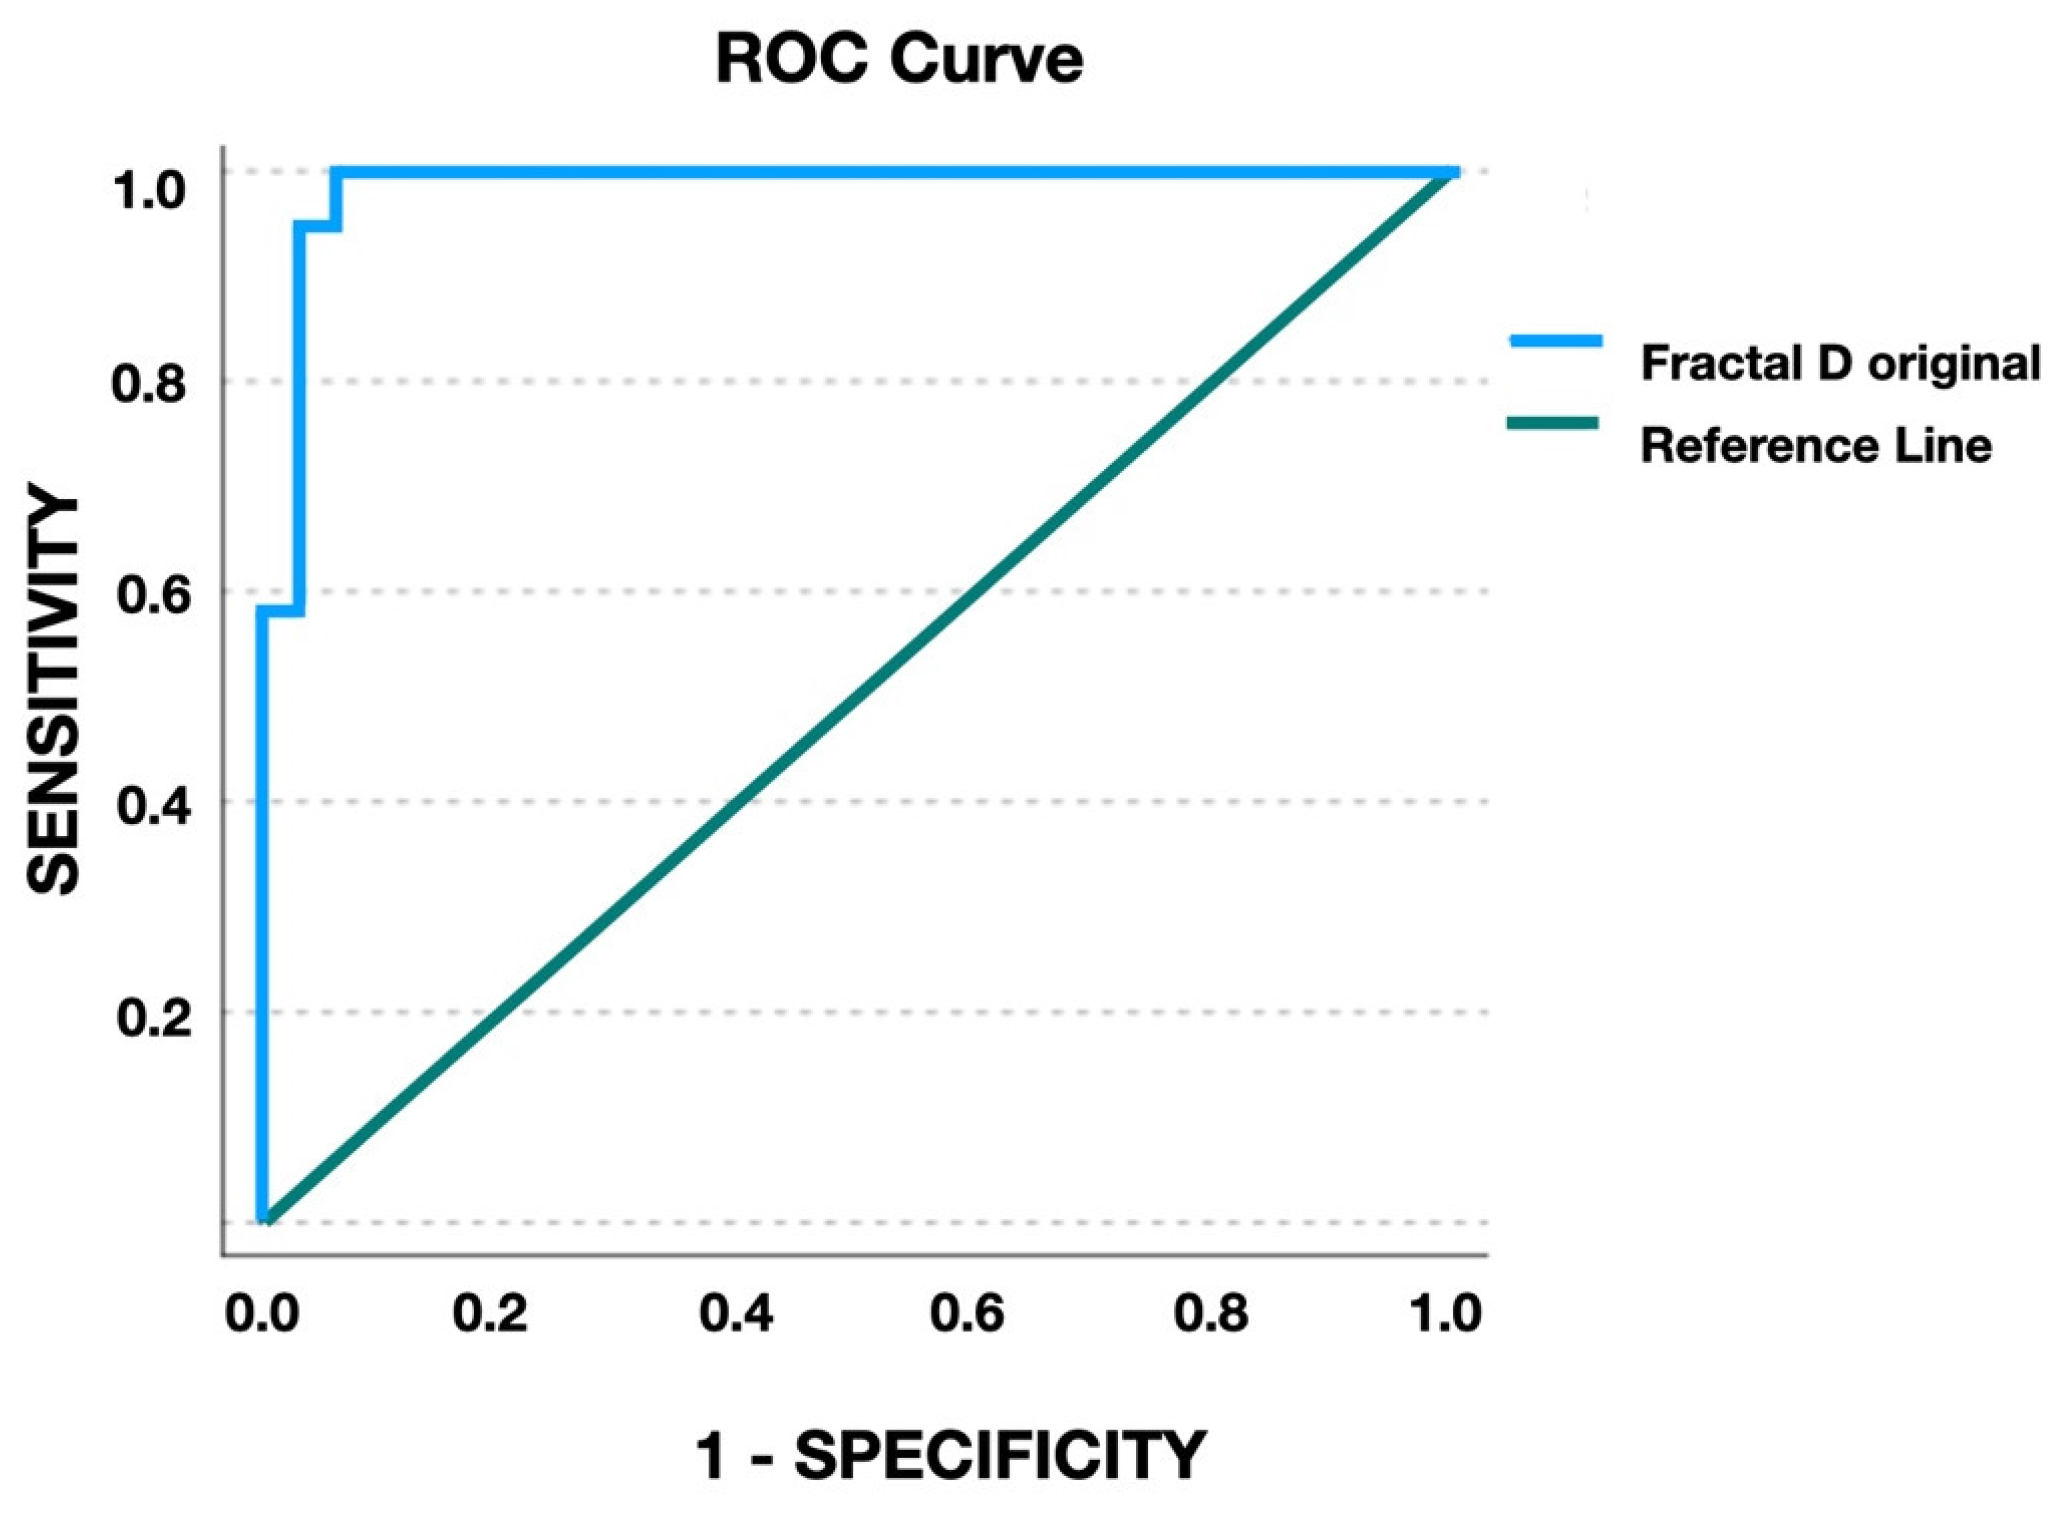

3.2. Agreement on MPS Stages and Fractal Dimension

- Kawak, K.H.; Kim, S.S.; Kim, Y.I.; Kim, I.D. Quantitative evaluation of midpalatal suture maturation via fractal analysis. Korean J. Orthod. 2016, 46, 323–330. [Google Scholar] [CrossRef]